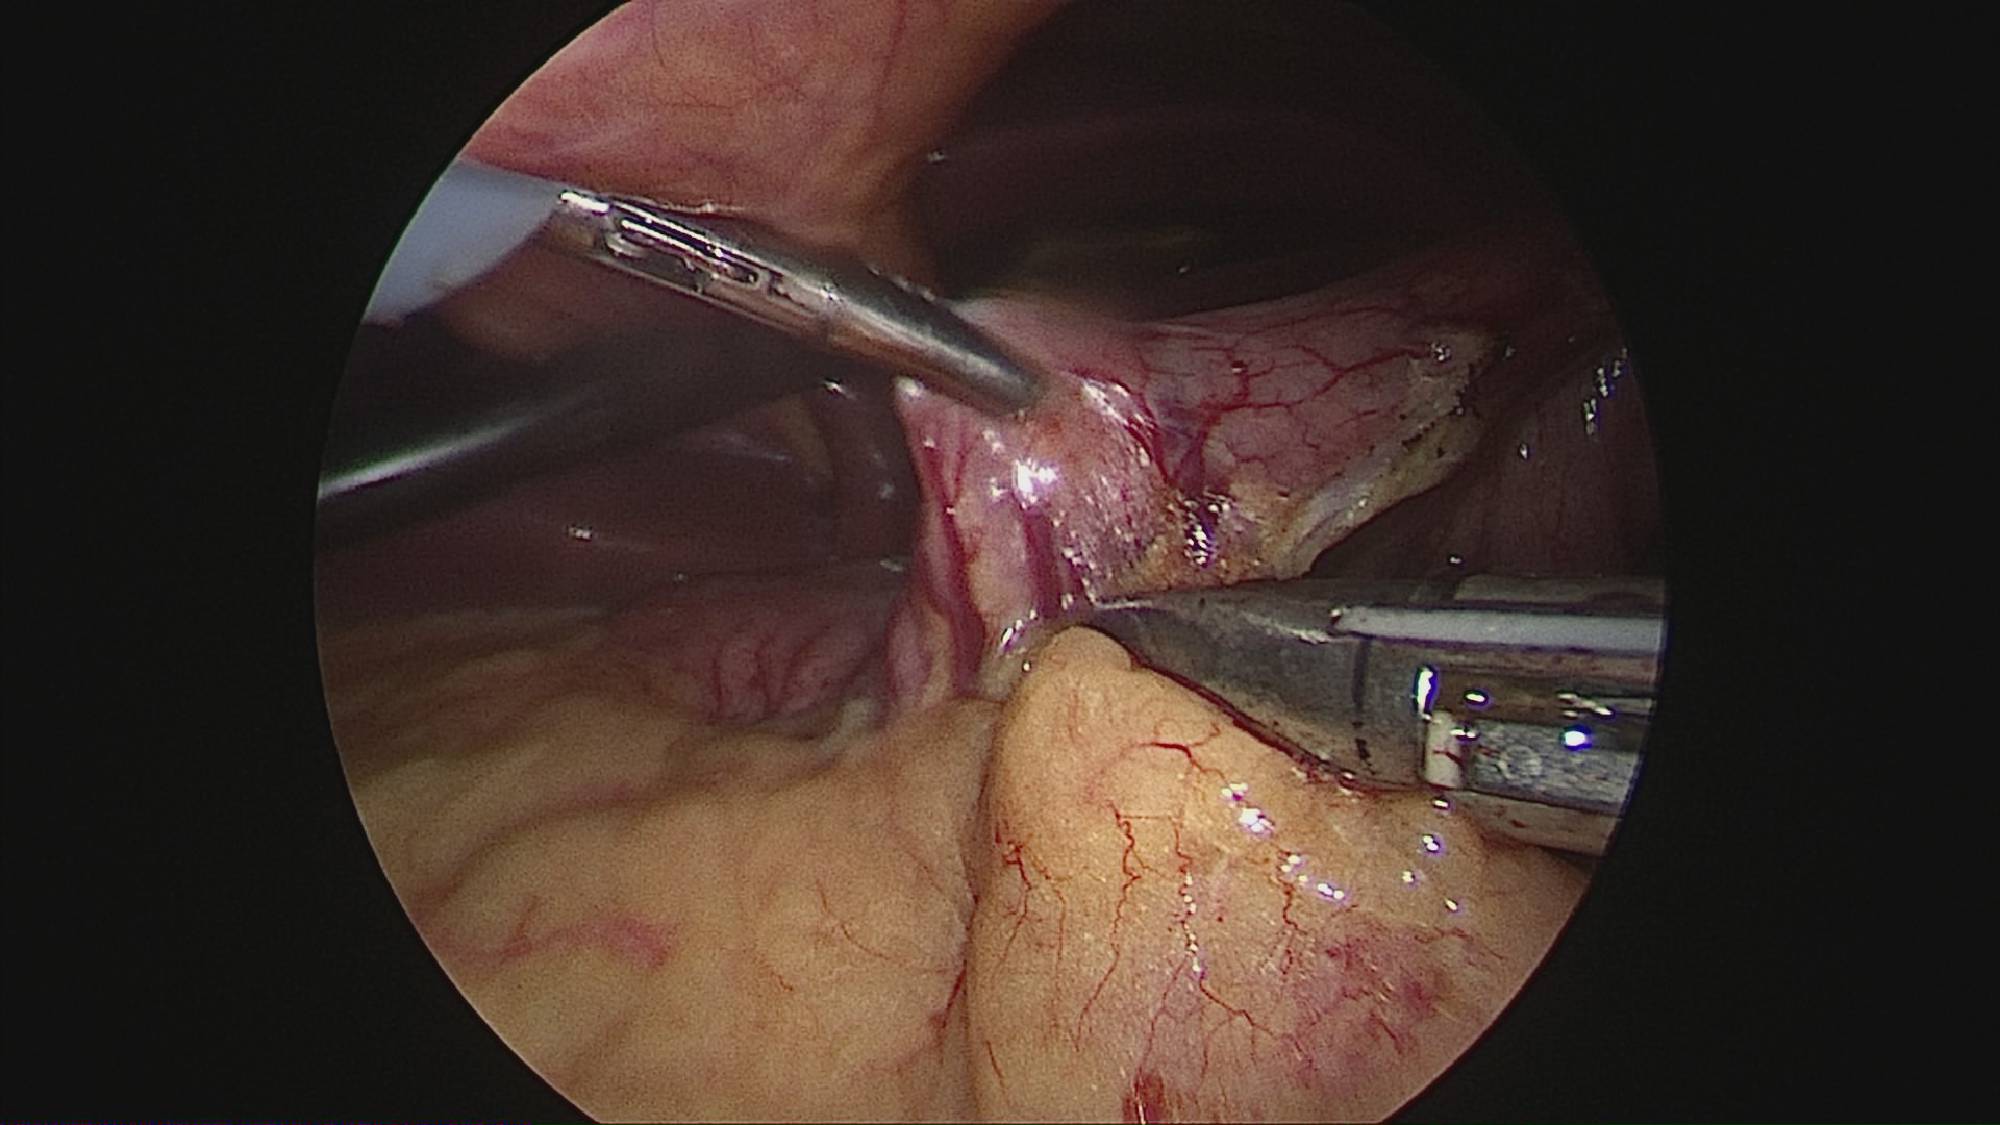

Gastrectomia longitudinală (gastric sleeve) este o intervenție care produce scăderea în greutate prin două mecanisme: restrictiv (îndepărtează o mare parte din stomac lăsând un rezervor de 80-120 ml) și hormonal (prin extirparea fundului gastric se reduce semnificativ secreția hormonului foamei, grelina).

Operația ”de micșorare a stomacului” se realizează miniminvaziv (laparoscopic) și constă în îndepărtarea marii curburi gastrice cu păstrarea antrului gastric și a micii curburi sub forma unui tub calibrat pe o sondă.